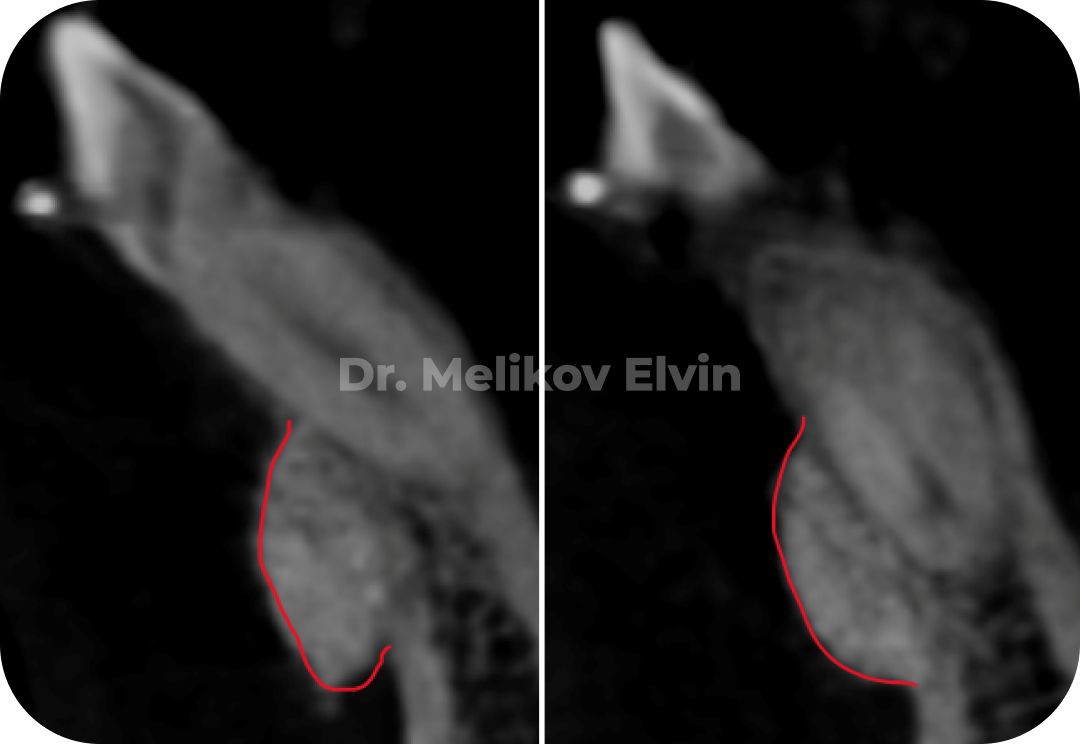

После костной пластики на двух челюстях

На снимках можно увидеть воссозданный объём наружной кортикальной пластинки в проекции корней зубов.